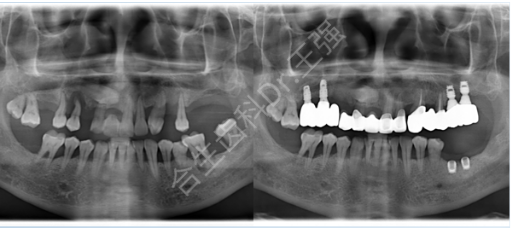

以下就是患有牙周炎、牙槽骨条件不佳、骨量不足的种植牙病例展示: